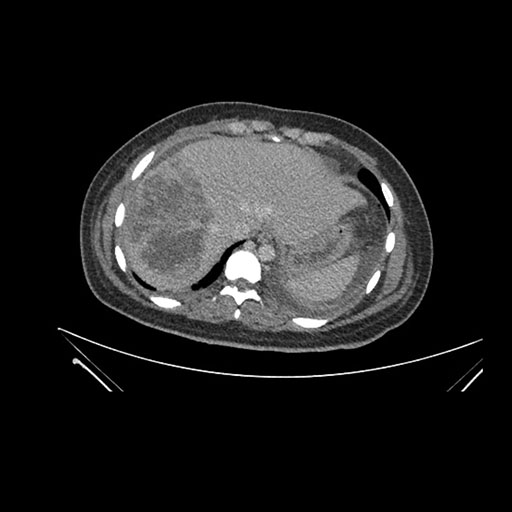

Axial Arterial

Axial Venous

Imaging analysis

Based on initial findings, which issue(s) would you be most concerned about?